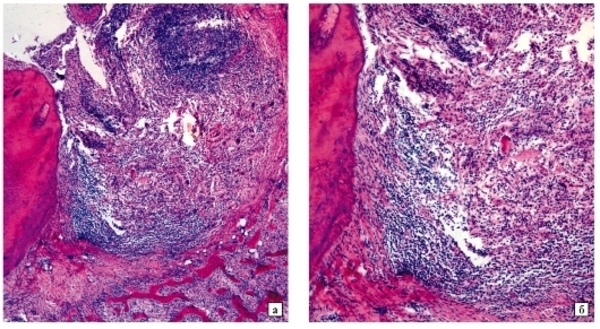

Фото 3. Патологическая анатомия или патанатомия зуба при периодонтите хронического типа. Зубные ткани показаны под микроскопом.